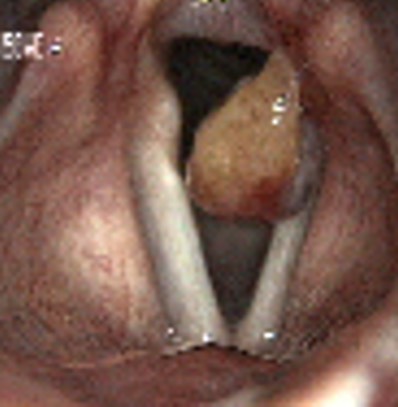

2643. Данная ларингеальная картина характеризует